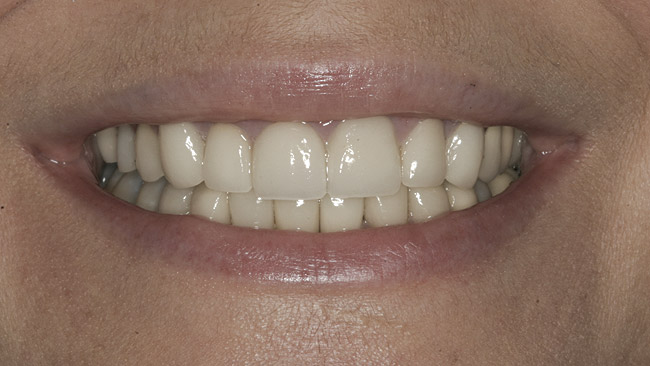

The final screw-retained crown was delivered and torqued onto the implant to 35 Ncm; the restorative dentist then sealed the screw access with a cotton pellet and composite (Figure 20 and Figure 21). Various views of the final crown are shown in Figure 22 through Figure 25, including a full-face photograph.

The patient, who works as a professional model, was pleased with her esthetic result, which was a paramount criterion for the team approach applied to this case, as emphasized by Vermylen et al, who reported positive to very positive ratings on esthetics and phonetics among 48 patients with 52 implants on which crowns were fabricated by their restorative dentists.12

The gingival frame of the final implant crown on tooth No. 9 successfully matched that of natural tooth No. 8 (Figure 23). Accomplishing this required not only preservation of the existing free-margin height, but also the mirroring of the zenith point (at the approximate junction of the middle and distal thirds of each incisor’s clinical crown).

Kinsel and Capoferri (restorative dentist and laboratory technician, respectively) emphasize maintaining the zenith with a harmonious FGM around implant crowns and adjacent teeth. They highlight the importance of provisional restoration contouring by the restorative dentist, and skillful modification of the master cast by the laboratory technician to emulate natural cementoenamel junction anatomy, whose convexity dictates the gingival frame.36 The provisional bis-acryl crown designed and fabricated by this patient’s restorative dentist enabled this elusive esthetic goal by introducing a slightly convex subgingival contour, establishing a lifelike emergence profile that was ultimately maintained in the definitive restoration (Figure 24).

Figure 22  Final zirconia crown, No. 9, in occlusion—facial view.

Figure 22

Figure 23  Final zirconia crown, No. 9—full-smile view.

Figure 23

Figure 24  Final zirconia crown, No. 9—distofacial lateral view; No. 8 midline recontouring—mesial aspect.

Figure 24

Figure 25  Patient in full smile showing final zirconia crown, No. 9—full-face view.

Figure 25